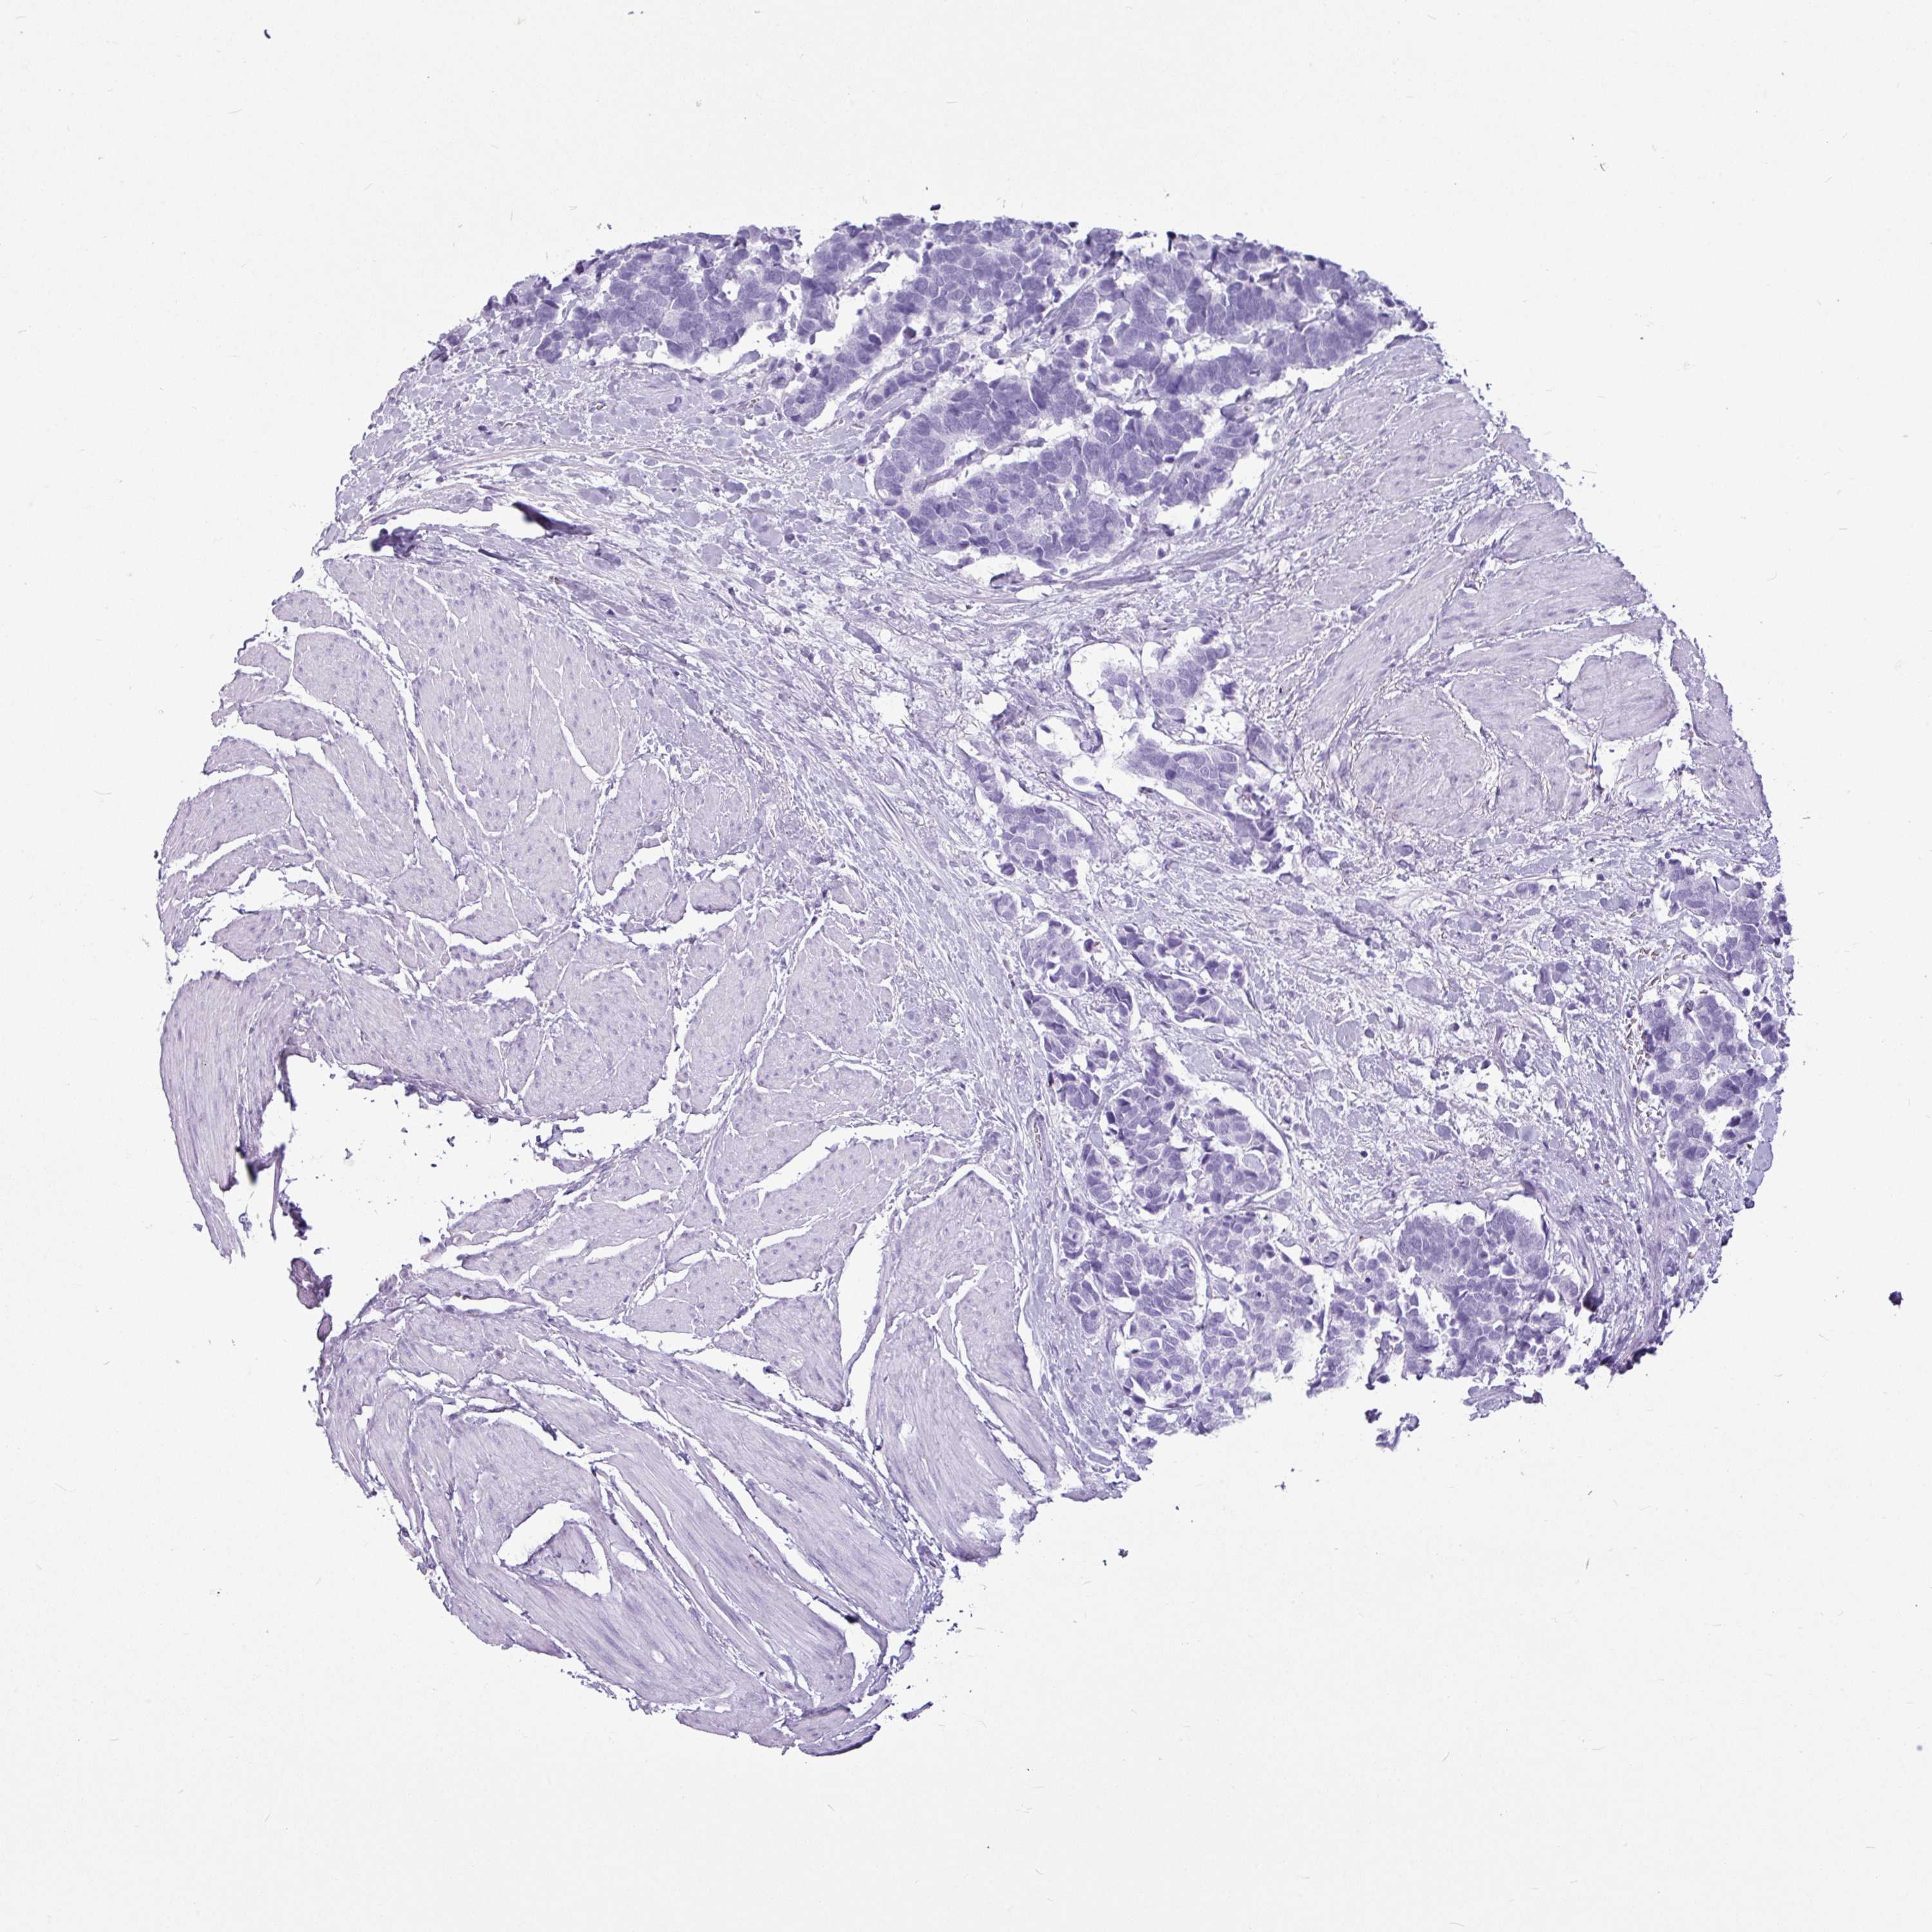

AMY1C